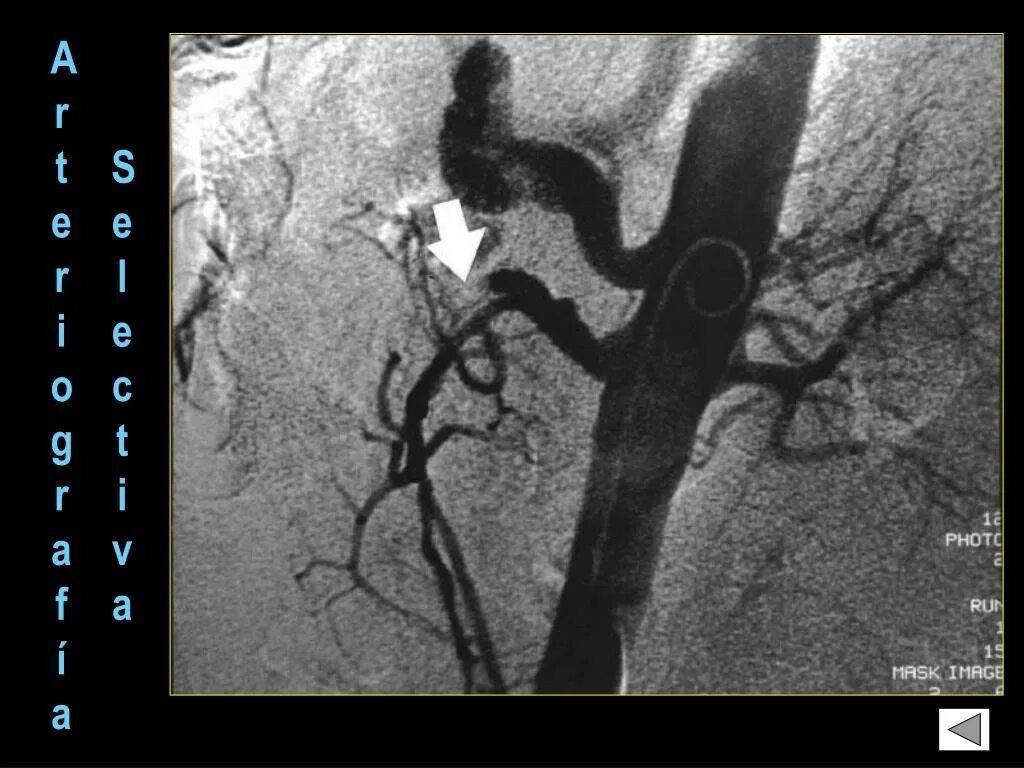

Тромбоз брыжеечной артерии